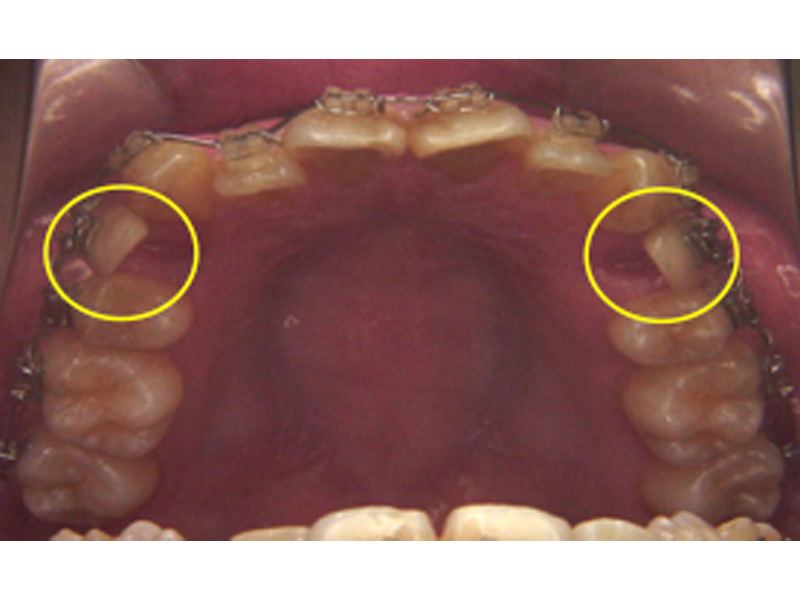

部分矯正(シニア矯正治療、MTM)

一般的な二次矯正は全ての歯の歯並び、咬み合わせを治しますが、部分治療の場合は、ブリッジや入れ歯などの補綴治療を前提として、その準備のために限局的な矯正治療を行います。